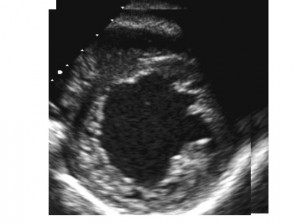

A transthoracic echocardiogram raised concerns about possible left-ventricular noncompaction.

LV systolic function was found to completely normal. However, the ratio of thick, noncompacted myocardium to thin, compacted myocardium was 1.7 in end-systole. (Jenni criteria include the presence of a maximum ratio of noncompacted-to-compacted myocardium >2 to 1 at end-systole in the parasternal short-axis view.)